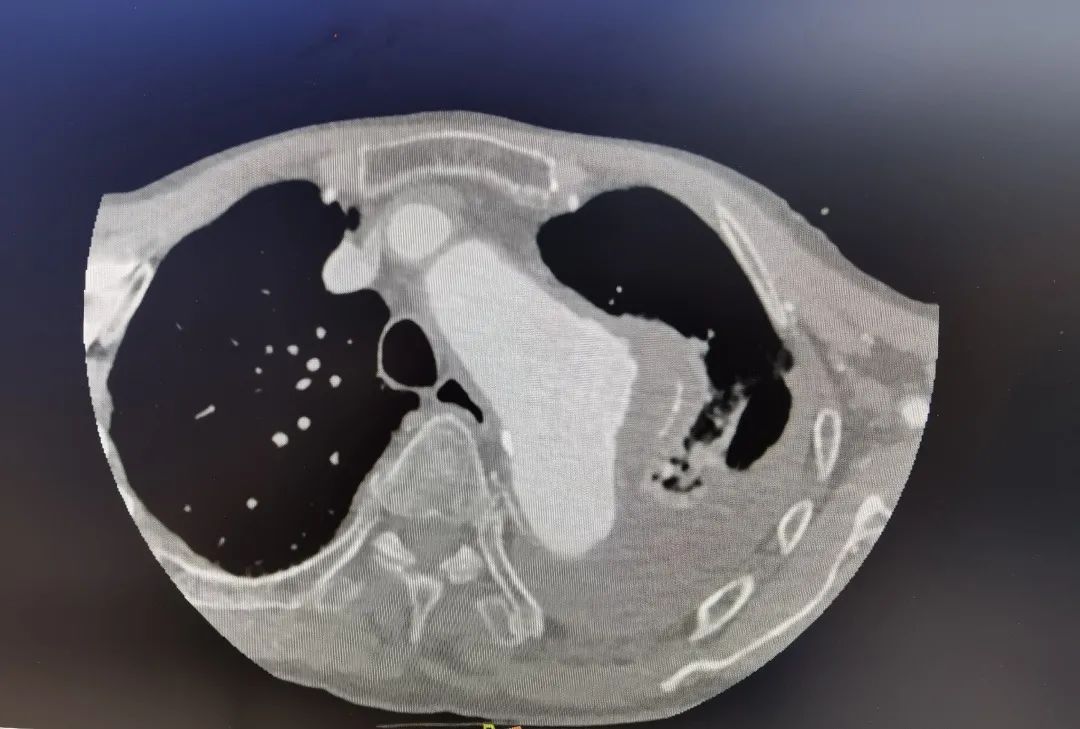

“患者被送到医院时,一直说胸口痛,如果体内有胸动脉瘤,这往往是瘤子要破裂的征兆。从CT影像来看也确实如此,造影剂已从主动脉瘤渗漏出来,说明瘤子即将破裂。另外,患者左侧胸腔大量积水,这也是动脉瘤破裂的先兆。”接诊的厦心心外科副主任医师伍源解释说,种种迹象表明,林大爷体内的动脉瘤随时可能破裂大出血迅速导致死亡,必须尽快手术。